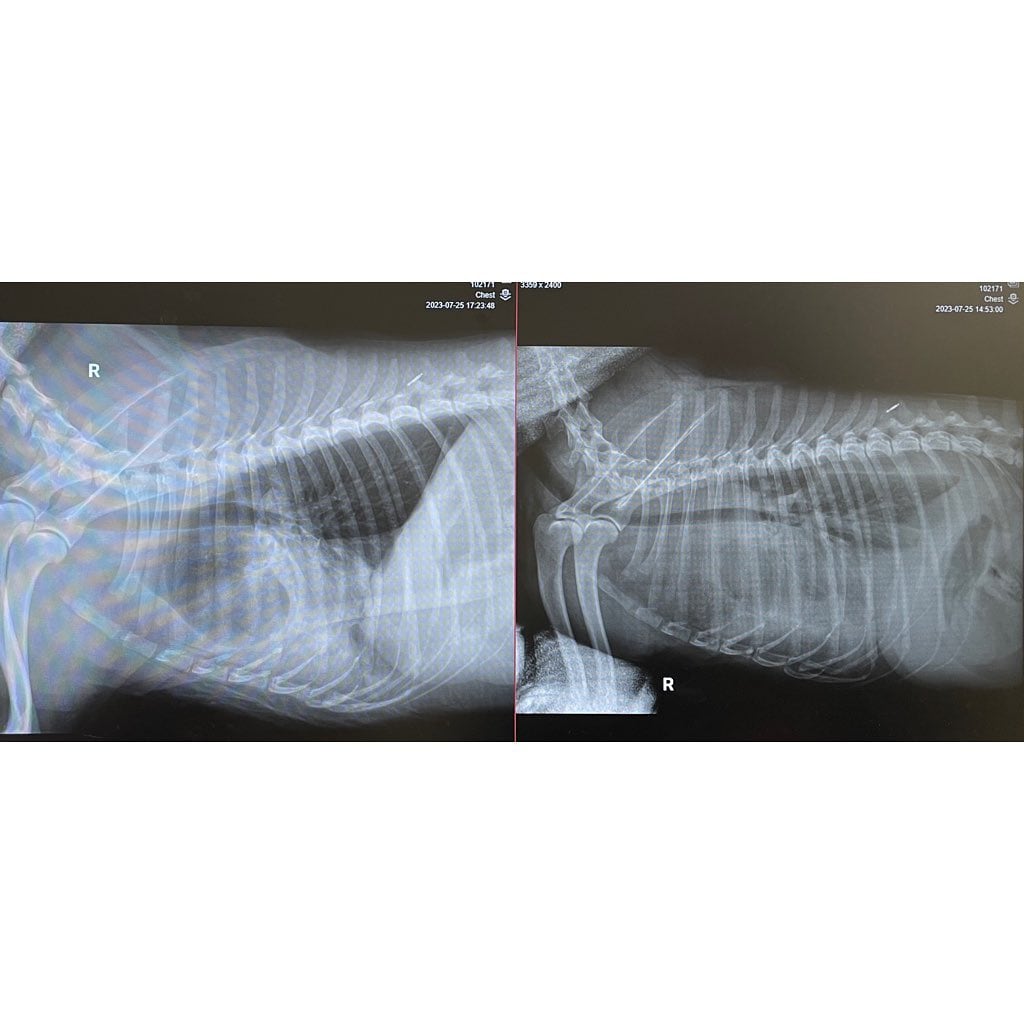

La publicación también estuvo acompañada de las radiografías que le han tomado al perrito Cheems recientemente y una explicación de lo que revelan:

“... las radiografías muestran que el líquido está presionando sus pulmones, ha bajado de 12,3 kg a 10,3 kg [de peso]”